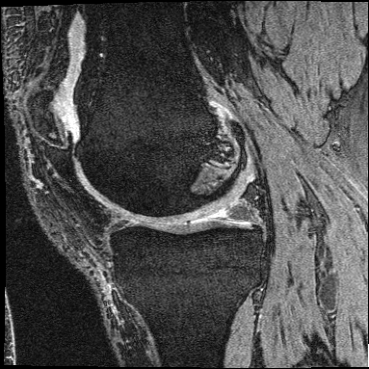

OAI Knee MRI We train and test on the split published with [22], with 2532 training examples and 301 test pairs from the Osteoarthritis Initiative (OAI) [16]444https://nda.nih.gov/oai. We evaluate using the mean Dice score of tibial and fibial cartilage. To compare directly to [22, 7, 23] we train and evaluate at [80x192x192].

| Moving Image | Warped Image | Fixed Image | Moving Image | Warped Image | Fixed Image |